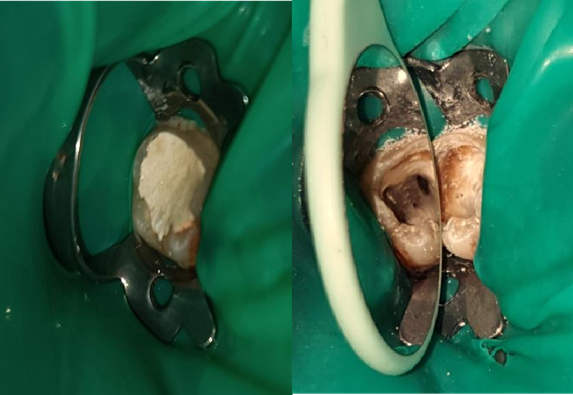

The instrument fracture prevented successful endodontic treatment of this tooth. In order to instrument and decontaminate the part of the canal beyond the fracture, we decided to remove the instrument from the canal. Briefly, rubber dam isolation and access cavity allowing for straight line access were performed (Figure 2).

Figure 2. Rubber dam isolation and access cavity.